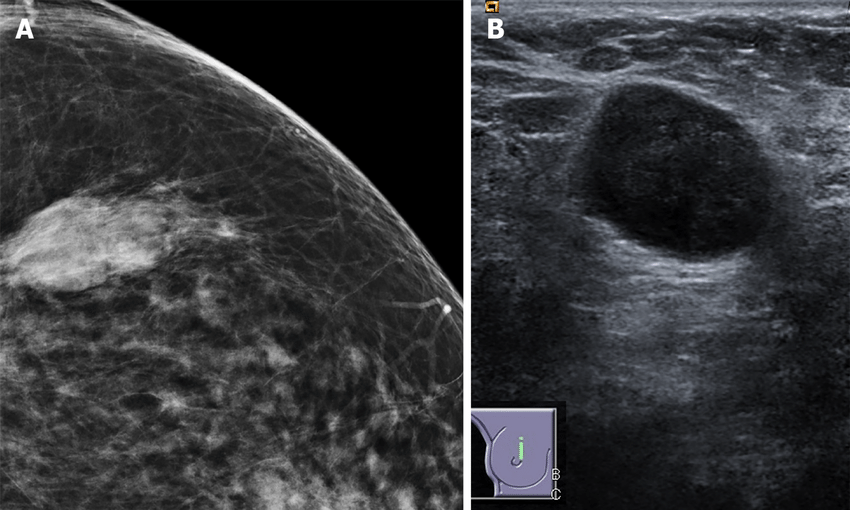

Bước đầu tiên có thể là chụp nhũ ảnh để đánh giá khối u hoặc cục u đáng ngờ trong vú của bạn. Dựa trên những gì họ tìm hiểu được, các nhà cung cấp dịch vụ chăm sóc sức khỏe có thể thực hiện sinh thiết để loại bỏ mô vú. Các nhà nghiên cứu bệnh học y khoa xác định phân nhóm bằng cách nghiên cứu các tế bào dưới kính hiển vi.